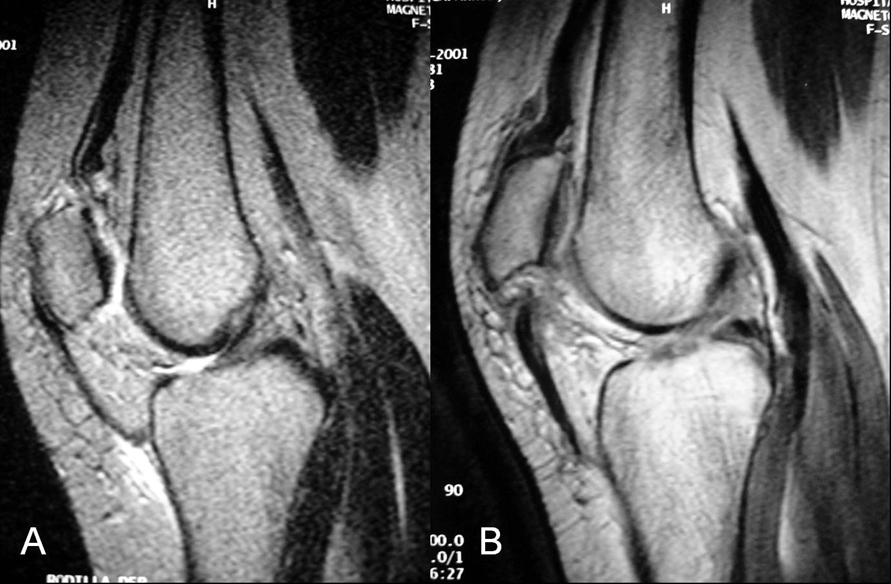

A 31-year-old female suffered sudden pain and loss of extension of both the knees after trying to get up from a sofa. No previous injuries of the knees or intensive sports activities were recorded. Her personal history consisted of chronic renal failure due to renal tubular acidosis diagnosed at the age of eight years and since then she was receiving maintenance hemodialysis until 1984, when a renal transplantation was performed. The transplantation failed six years later and a transplantectomy was performed. Since then, the patient underwent dialysis and recently, a tertiary hyperparathyroidism was detected, with high levels (2332 pg/mL) of parathyroid hormone (PTH), and a parathyroidectomy was proposed for its correction. Physical examination revealed local pain, swelling and lack of active extension. Laboratory examination was normal except for a normocytic anemia, creatinine of 1.6 mg/dL and serum calcium of 11.6 mEq/L. Radiographic examination revealed a high patella in the left knee and a low patella in the right knee (Figure 1). Insall-Salvati index was 0.65 for the right knee and 1.35 for the left knee. Magnetic resonance imaging (MRI) showed a complete rupture of the left patellar tendon at its proximal insertion and the avulsion of the right quadriceps tendon at its patellar insertion (Figure 2). The patient was operated and repair of both the tendons was performed. We observed that the rupture was present at the level of bone-tendon junction without an associated fracture. Tissue samples were obtained for pathological study. We performed the repair of the tendons using heavy nonabsorbable sutures, maintaining the original insertional point in order to avoid tilting of the patella. No additional reinforcing systems were used. At the end of the operation, the flexion grade of both knees was correct, without failure of the sutures during the passive mobilization. Pathological study revealed chronic degenerative changes, with no other specific alterations. Both legs were immobilized with plaster cast and walking with full weight-bearing was permitted at six weeks. One month after surgery, the patient underwent a surgical removal of the parathyroid glands, followed by a progressive normalization of the PTH levels. After four months follow-up, autonomous deambulation was possible without aids, and the range of movement was 0 to 70 degrees in the right knee and 0 to 90 degrees in the left knee. After ten months follow-up, a slight improvement in the range of movement was noticed for both knees (0 to 100 degrees) the patient was able to walk free of pain and was being satisfied with the results.

Figure 1: (A) Lateral radiograph showing a low patella in the right knee and, (B) A high patella in the left knee.